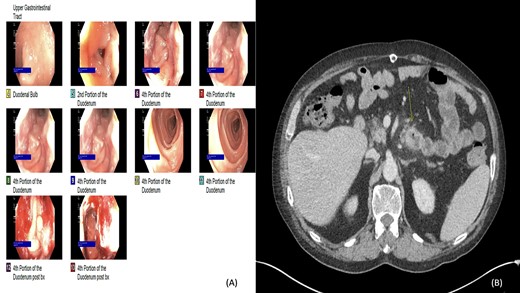

Two years later, the patient presented again with abdominal pain and rectal bleeding. On CT scan of abdomen and pelvis a lobular circumferential enhancing mass of the proximal fourth portion of the duodenum, with shotty adjacent lymph nodes was found, that was suspicious for primary duodenal adenocarcinoma. As part of diagnostic workup, the patient underwent an EGD (Fig. 2). The biopsy confirmed the presence of invasive moderately differentiated adenocarcinoma and immunohistochemistry testing for mismatch repair proteins (MMR) was significant for the loss of nuclear expression of PMS2 (Fig. 3). The patient underwent resection of the small bowel between the ligament of Treitz and the previous jejunojejunostomy site and end-to-side duodenojejunostomy was performed between the end of the fourth portion of the duodenum and the side of the distal limb of the Roux-en-Y portion of bowel that had previously been created for the hepaticojejunostomy, to reestablish intestinal continuity.

(A and B) Esophagogastroduodenoscopy (EGD) and computed tomography: lobular circumferential enhancing mass of the proximal fourth portion of the duodenum.